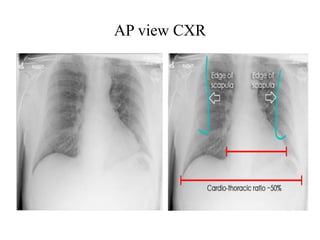

2. AP VIEW:

Lower quality

 Heart magnification (farther from film)

 Clavicles are projected more cranially above

lung apex

 Scapulae overlie lung fields

 Ribs appear horizontal

 Gastric bubble is absent

AP Projection

AP view CXR

 Size measurement:

• CT ratio: < 50%

• Transverse cardiac

diameter:

< 15.5 cm (M)

< 14.5 cm (F)

 Heart size appears

enlarged on expiration,

supine film, AP film &

when diaphragms are

elevated